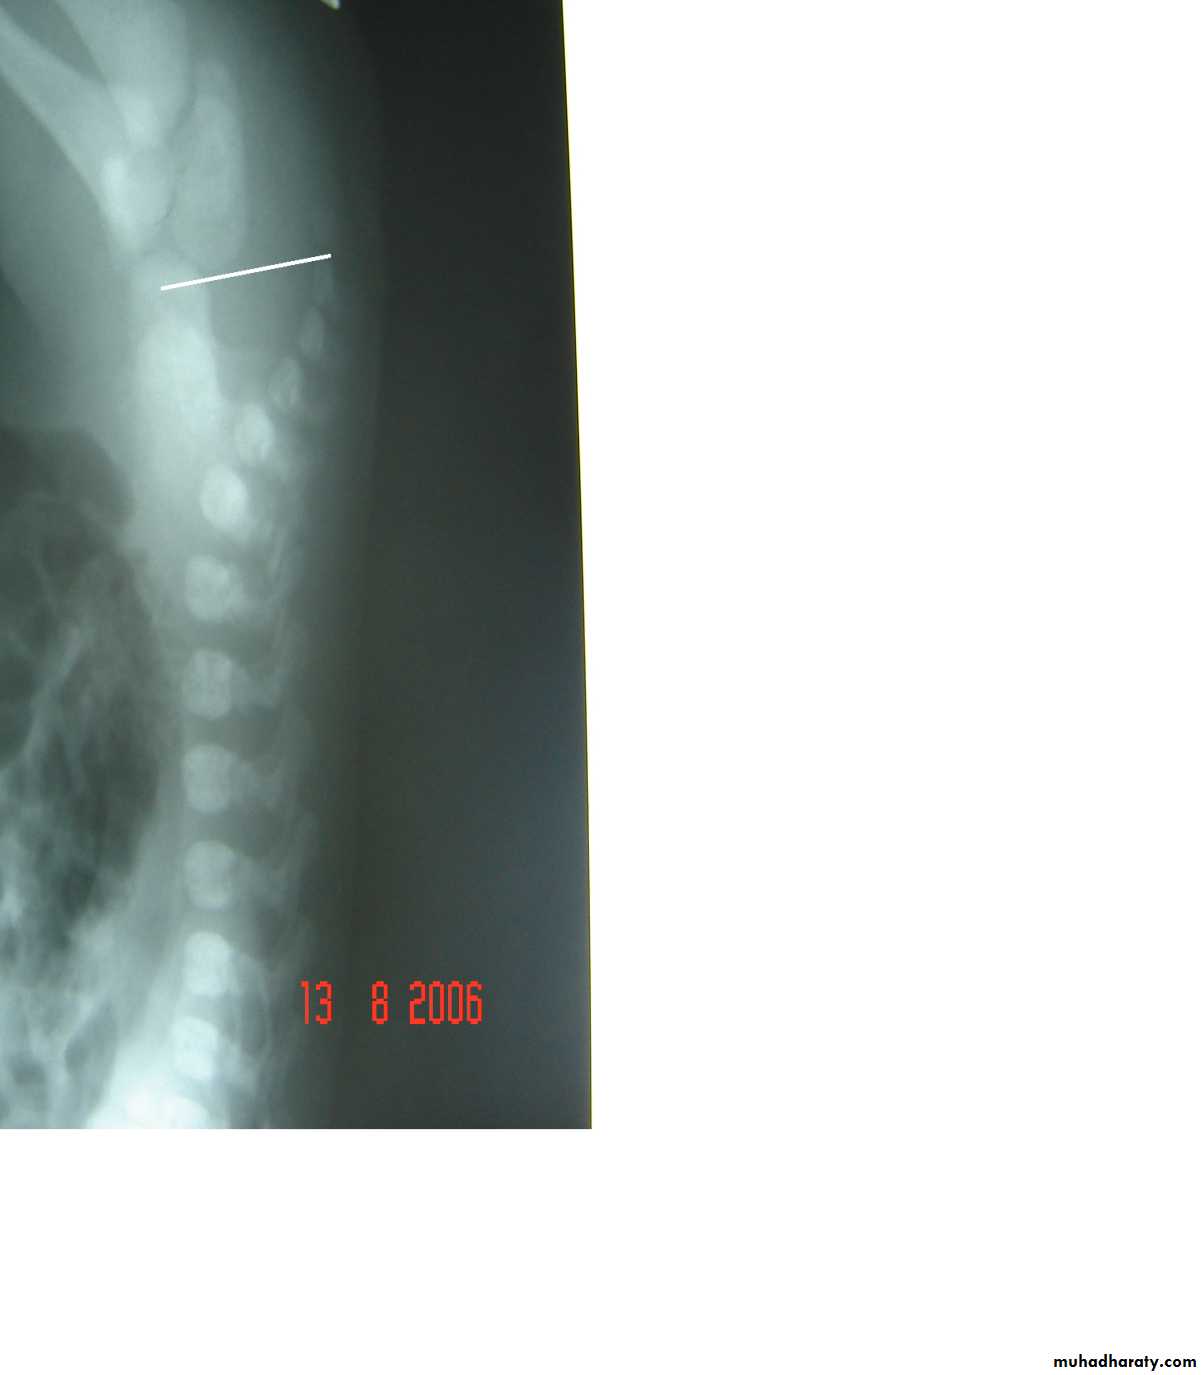

Anorectal Anomalies

First and second photos:

Lateral invertogrampubococcygeal line

It is low type

Third photo:

Lateral decubitus x-ray

Low type

Anal dimplePass of meconium through the urethra

High typeSubcutaneous meconium – cutaneous fistula – low type